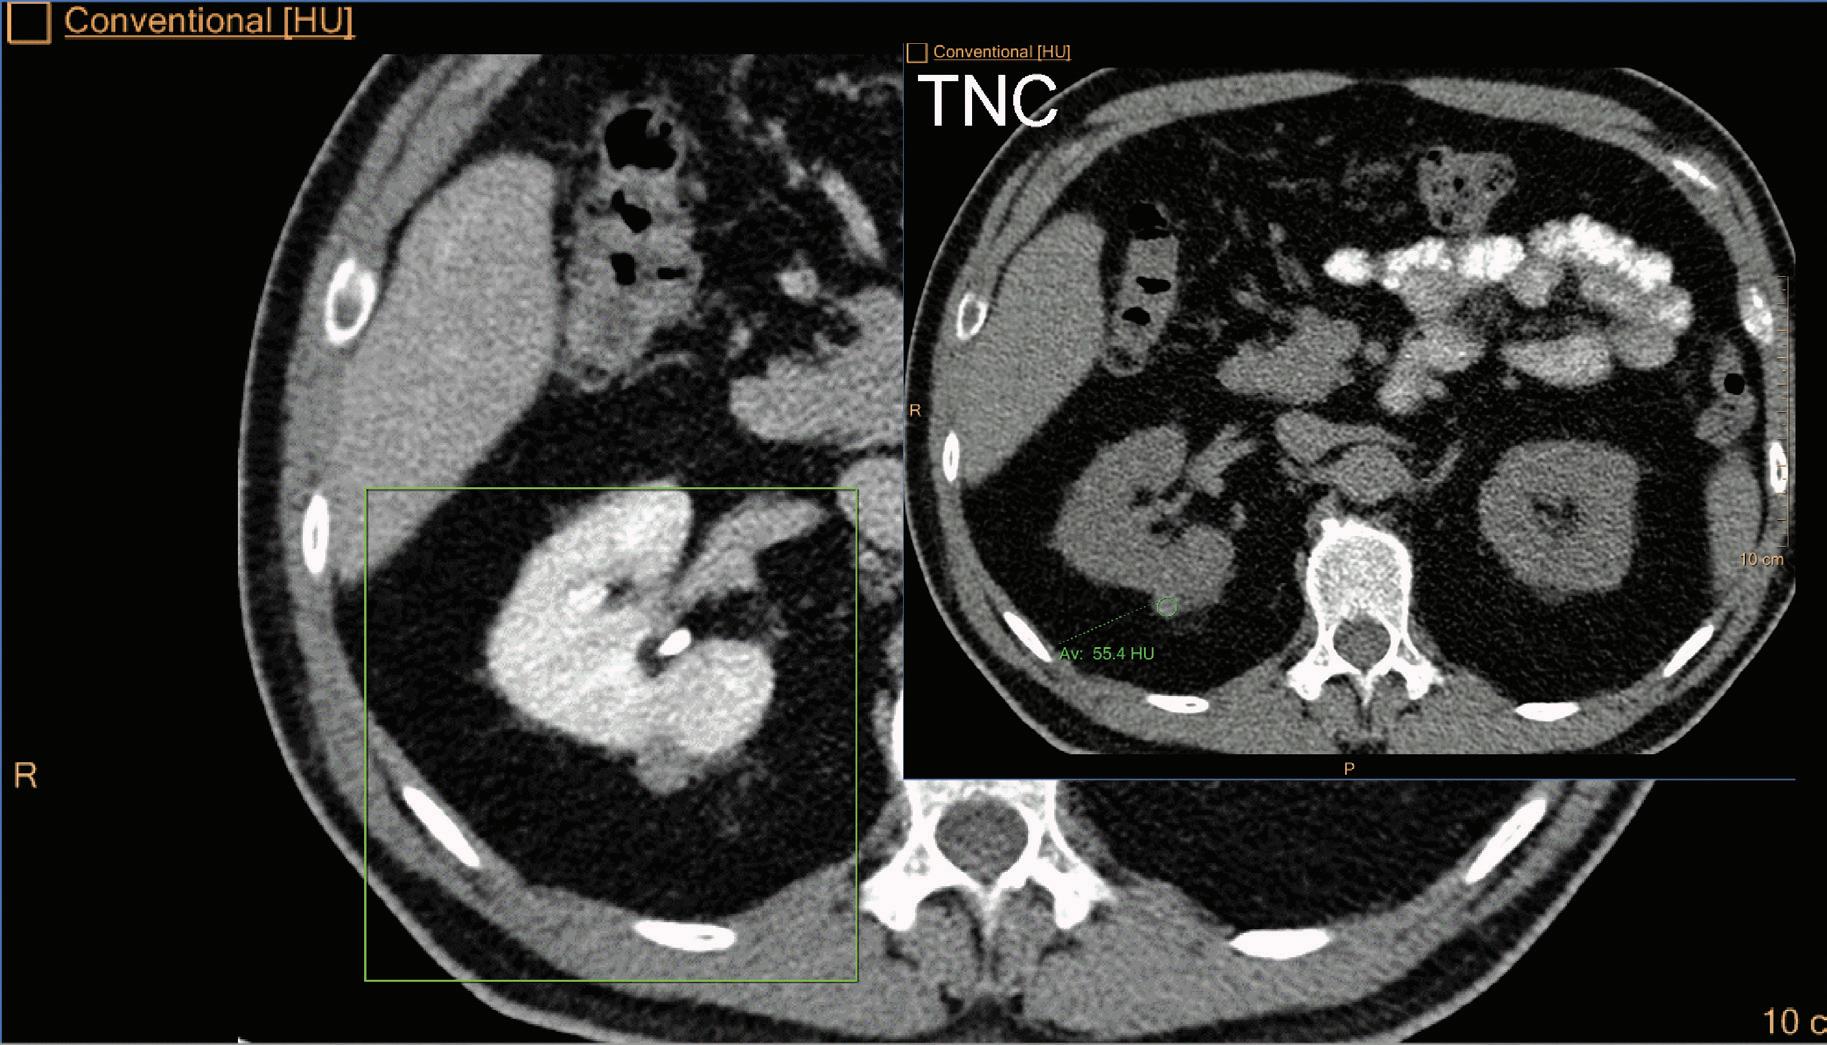

Virtual No Contrast (VNC) [HU]

This result imitates a monoenergetic 70 keV CT scan without contrast injection, and is derived from a CT scan with contrast enhancement. The quantified iodine content is translated to an HU number and subtracted from the contrast enhanced 70 keV images.

Note: Because the iodine quantification is based on the two-component model (water-iodine), any deviation from water dispersion is interpreted as nonzero iodine component. In particular, bone (calcium) is interpreted as a mixture of water-like and iodine-like material. The VNC algorithm does not attempt to separate bone and iodine. Therefore, the CT number [HU] of bone in VNC images is roughly half of its value in the original 70 keV image. A study comparing VNC and true non-contrast (TNC) images showed that the attenuation values from VNC in most abdominal tissues are within 10 HU of those obtained from unenhanced images, with the notable exception of subcutaneous fat.11,12 These results demonstrate the potential of VNC images to serve as a surrogate for unenhanced images in some clinical settings (Figure 4).

A hyperdense lesion (65 HU) is visible on the right kidney on the conventional CT images obtained after contrast enhancement. The TNC image is shown in the upper right corner. The lower row displays spectral results in the Magic Glass, from left to right: conventional CT image, VNC image, Iodine no Water image, and iodine density image. Comparison between measurements performed on the TNC (55.4 HU) and VNC images (57.6 HU) demonstrates only a minor difference between them (difference = 2.2 HU), showing that the VNC images could perfectly replace the TNC images in this clinical scenario. Iodine concentration measurements in the same region of interest show values of no more than 0.3 mg/ml which can be considered as negligible. In other words, there is no contrast medium uptake in the lesion which can thus be considered as benign. The hyperdensity is of a hemorrhagic cyst.